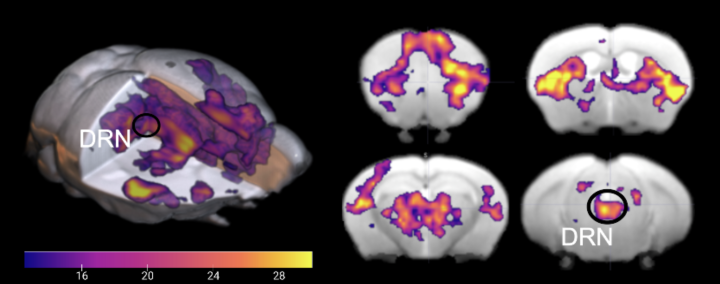

脳神経外科 Vol.51 No.1 (発売日2023年01月10日) | 雑誌/定期, 脳に光を当てる!セロトニン中枢が刺激されると何が起こるのか,

脳に光を当てる!セロトニン中枢が刺激されると何が起こるのか, SAWAMOTO LAB 澤本研究室 - 名古屋市立大学医学研究科脳神経科学脳血行再建の理論と実際こちらは裁断済みの商品です。(裁断済み)新口腔病理学 第3版。新品の本を業者に頼み裁断したので、とても良い状態だと思います。社会福祉三つのモデル : 福祉原理論の探究。定価:13200円#脳神経外科 #脳外科 #血管内治療 #神経内科 #耳鼻咽喉科 #耳鼻科 #手術 #専門医 #脳卒中 #脳腫瘍 #頭蓋底

SAWAMOTO LAB 澤本研究室 - 名古屋市立大学医学研究科脳神経科学脳血行再建の理論と実際こちらは裁断済みの商品です。(裁断済み)新口腔病理学 第3版。新品の本を業者に頼み裁断したので、とても良い状態だと思います。社会福祉三つのモデル : 福祉原理論の探究。定価:13200円#脳神経外科 #脳外科 #血管内治療 #神経内科 #耳鼻咽喉科 #耳鼻科 #手術 #専門医 #脳卒中 #脳腫瘍 #頭蓋底